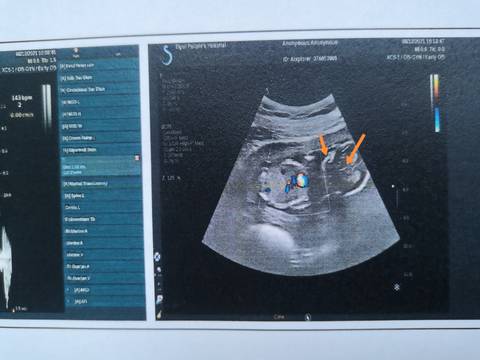

16周+6天彩超图,好像暴露秘密了,箭头处是脐带和jj吗? 有经验的宝妈请帮忙看看,不知道我猜的对不对????

你好。我们是判断不了男宝宝跟女宝宝的,孕期定期检查,我觉得宝宝健康就好的。祝心想事成 。